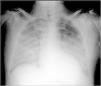

Case reportA 62-year-old Caucasian male underwent conventional aortic valve replacement using a stented bioprosthesis (standard 23 mm Carpentier-Edwards Perimount) six years ago, as suggested by the cardiac surgeons, in order to avoid oral anticoagulation. Transthoracic echocardiography performed six months before admission showed normal left ventricular ejection fraction with a normally functioning aortic bioprosthesis and slightly elevated gradients (mean pressure gradient 18 mmHg). The patient was referred to the emergency department of our hospital in cardiogenic shock complicated by pulmonary edema (Figure 1) and was immediately treated with diuretics and high-dose inotropes to achieve stabilization.